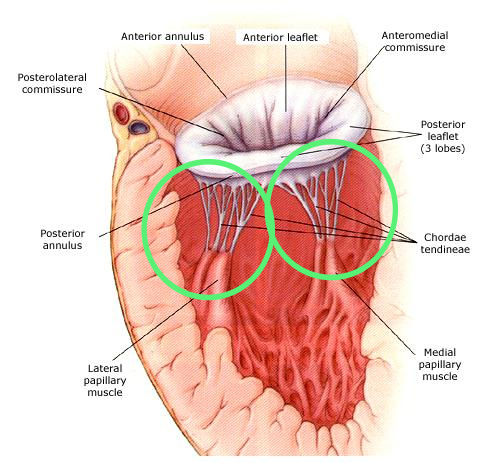

Mitral Valve Basal Chordae: Comparative Anatomy And Terminology - The

www.annalsthoracicsurgery.org

www.annalsthoracicsurgery.org

basal chordae mitral valve anatomy comparative terminology

Mitral Valve Chordae Tendineae. (a) Subvalvular Apparatus, View Of The

www.researchgate.net

www.researchgate.net

mitral anterior leaflet position subvalvular annulus surgical biomechanical